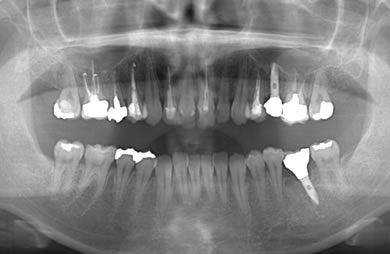

インプラントの症例写真 IMPLANT

骨再生インプラント治療+セラミック治療

| 治療方針 | 左側の奥歯の部分の歯が欠如しているのでインプラント治療にて機能的・審美的回復を行いつつ、その他の虫歯の部分はセラミック歯にて治療を行う。 | ||||||||||||||||||||||||||||||||

| 治療内容 | インプラント2本(ソケットリフト)、ハイブリッドセラミック2本、オールセラミック3本(オールセラミック用の土台3本)、メタルボンドセラミック2本(メタルボンドセラミック用の土台1本) | ||||||||||||||||||||||||||||||||

| 総治療費 | 1,662,900円 | ||||||||||||||||||||||||||||||||

| 治療期間 | 1年7ヶ月 |